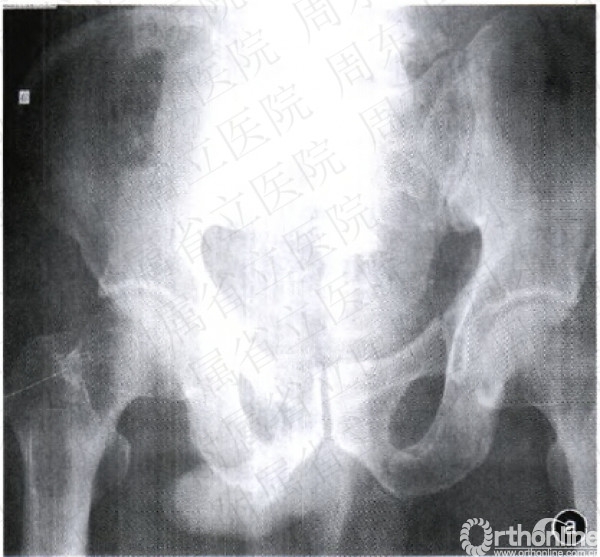

图l纱布填塞术止血手术及示意图a竹Z}Ir位x线片示Tile分型的B型骨盆骨折b急诊行纱布填塞术进行止血c示意图示取腹部正中切ICl(也可取耻骨上横切口和髂腹股沟切口),牵开腹膜,在腹膜外进行填塞d示意图示纱布填塞的位置:耻骨后方、髂窝及骨盆环与腹膜之间的腹膜外间隙e填塞术后行CT检查示纱布填塞于耻骨后方

对于剖腹探查患者,直接于剖腹探查切口进行填塞,填塞物直接压迫髂内动脉分支与骶前静脉丛(图1a一1c)。对于非剖腹探查患者,根据骨折类型判断出血部位,前环损伤出血则在耻骨联合上方约2cm处做一长约8em的横切口,将填塞物置于耻骨后方进行压迫止血。而对于后环损伤导致的出血则取髂腹股沟切口,逐层分离两侧腹膜外间隙至两侧骶髂关节前方,注意保持腹膜完整。将填塞物(无菌纱布或绷带)于腹膜外间隙,置于骶前、骶髂关节直至耻骨后方(图1d,1e)。填塞物直接压迫髂内动脉分支与骶前静脉丛。对侧同样进行填塞。填塞完毕后,连续缝合法逐层关闭皮下组织与皮肤。